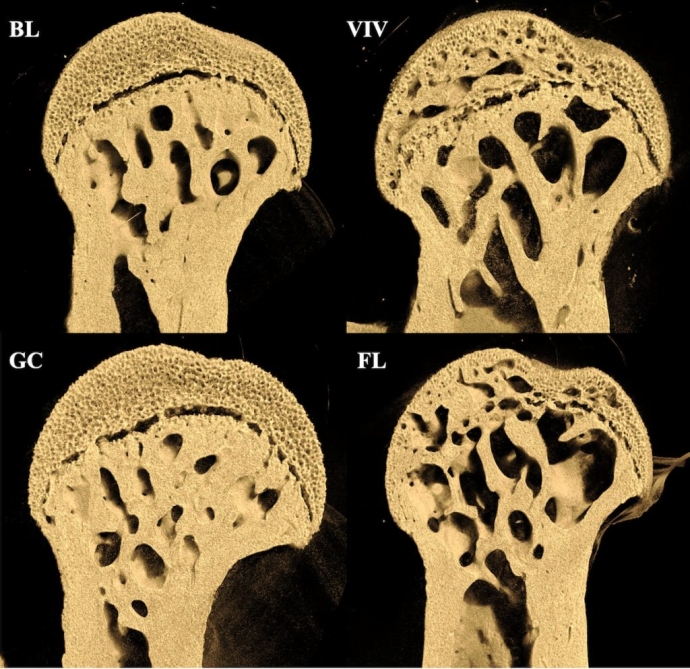

ИзображениеГоловка бедренной кости у мышей из четырех групп: сравнение мышей, которые провели на МКС 37 дней (FL), с грызунами, которые находились на орбите в течение одного дня (BL), наземными контрольными мышами (GC) и наземными контрольными мышами, содержавшимися в клетке, ограничивающей движение (VIV). Изображение: Rukmani Cahill et al., PLOS One

Эксперимент стал самым продолжительным исследованием влияния невесомости на грызунов. Ученые провели микрокомпьютерную томографию и гистологический анализ костей мышей, сравнив их с контрольными группами на Земле. Результаты показали выраженную потерю как губчатой, так и кортикальной костной ткани в бедренной кости — основном элементе опорного скелета у четвероногих животных. При этом позвоночник (в частности, второй поясничный позвонок) практически не пострадал.

Результаты наблюдению указывают, что потеря костной массы в условиях невесомости в первую очередь обусловлена отсутствием механической нагрузки, а не системными факторами вроде радиации. Если бы воздействие исходило извне, например от ионизирующего излучения, разрушения шли бы с поверхности кости внутрь. Однако наблюдалась обратная картина — кости разрушались изнутри наружу.

Ученые также зафиксировали неожиданный эффект преждевременного окостенения эпифизарной пластины — области роста в головке бедренной кости. Это значит, что микрогравитация может вызывать ускоренное завершение роста длинных костей у организмов, находящихся на поздних стадиях скелетного созревания.

Интересно, что мыши, находившиеся на Земле, но в условиях ограничивающих движения демонстрировали схожую потерю костной массы. Это подтверждает гипотезу, что механическая стимуляция через движение и сопротивление — ключевой фактор поддержания здоровья костей.